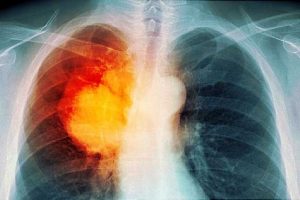

یک متخصص ریه گفت: سرطان ریه یکی از سرطانهای شایع است که با مصرف برخی نوشیدنیها میتوان ریسک ابتلا به این بیماری را کاهش داد.

به گزارش کرج رسا، سید جواد علیموسوی در گفتگو با باشگاه خبرنگاران جوان درباره بیماری سرطان ریه گفت: سرطان ریه یکی از سرطانهای شایع و رایج در میان افراد است که طبق مطالعات و پژوهشهای انجام شده در سالهای اخیر این نوع سرطان در جهان رو به افزایش است.